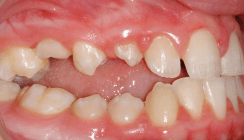

In der Behandlung von Milchzahn- und Wechselgebissen muss die Therapie und Stabilität eines frontal offenen Bisses anders angegangen werden als im bleibenden Gebiss, da die dentoskelettale Reaktion auf die Behandlung und die Stabilität anders sind.16

Die Behandlung im Milchzahn- und Wechselgebiss kann wie folgt zusammengefasst werden: Vor einem Alter von fünf Jahren sollten keine Apparaturen eingesetzt werden. Es wird lediglich eine Belohnungsstrategie empfohlen, d.h. vorzuschlagen, die Gewohnheit des Daumen- oder Schnullerlutschens gegen ein Spielzeug einzutauschen, das das Kind haben will.9 Ab einem Alter von fünf Jahren muss die Gewohnheit mithilfe einer Gaumenklammer oder Zungenspornen abgewöhnt werden.19 Wenn aufgrund einer Nasenblockade ein Mundatmungsproblem besteht, sollte das Kind zur Behandlung an einen Hals-Nasen-Ohren-Facharzt überwiesen werden. Nach Schließung des offenen Bisses sollte eine Sprach- oder Muskelfunktionsbehandlung eingeleitet werden, wenn die oralen Funktionsprobleme nach der Formungskorrektur nicht abklingen.23 Bei der Verwendung einer Gaumenklammer oder von Zungenspornen schließt sich der Biss, da die mechanischen Hindernisse, die der Daumen oder Schnuller und das falsche Zungenpressen bzw. die falsche Zungenstellung darstellten, beseitigt wurden und die Frontzähne wieder zu ihrer normalen vertikalen Entwicklung zurückfinden20 (Abb. 1a, b). Die klinische Stabilität der Behandlung beträgt nahezu 100 %6,11 und daher besteht kein Bedarf für eine zusätzliche Strategie zur Verbesserung. Die klinische Stabilität bezieht sich auf den Prozentsatz der Patienten, die langfristig einen positiven Überbiss haben.